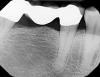

Fig. 27 through Fig. 30 The radiograph shows a periapical radiolucency. Three slices from the CBCT show a clear root fracture and buccal fistula showing an unrestorable tooth. With the CBCT information, the doctor can explain alternatives to the patient and not be surprised at the time of surgery.

Figure 27

Figure 28

Figure 30